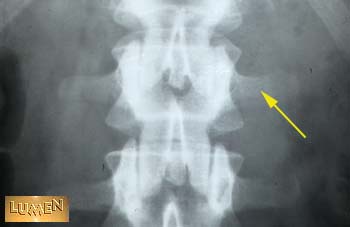

Identify the structure indicated by the arrow.

Transverse process.